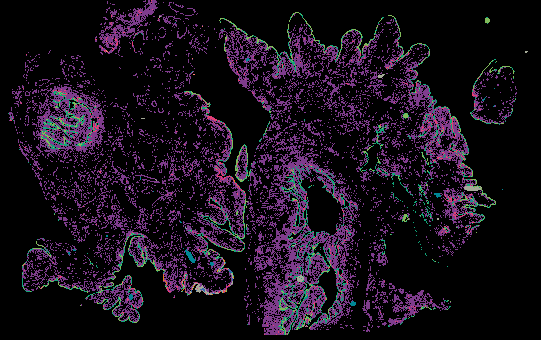

Serous Tubal Intraepithelial Carcinoma (STIC) with BRCA2 Mutation (LSP18251) from 'Multimodal Spatial Profiling Reveals Immune Suppression and Microenvironment Remodeling in Fallopian Tube Precursors to High-Grade Serous Ovarian Carcinoma'.